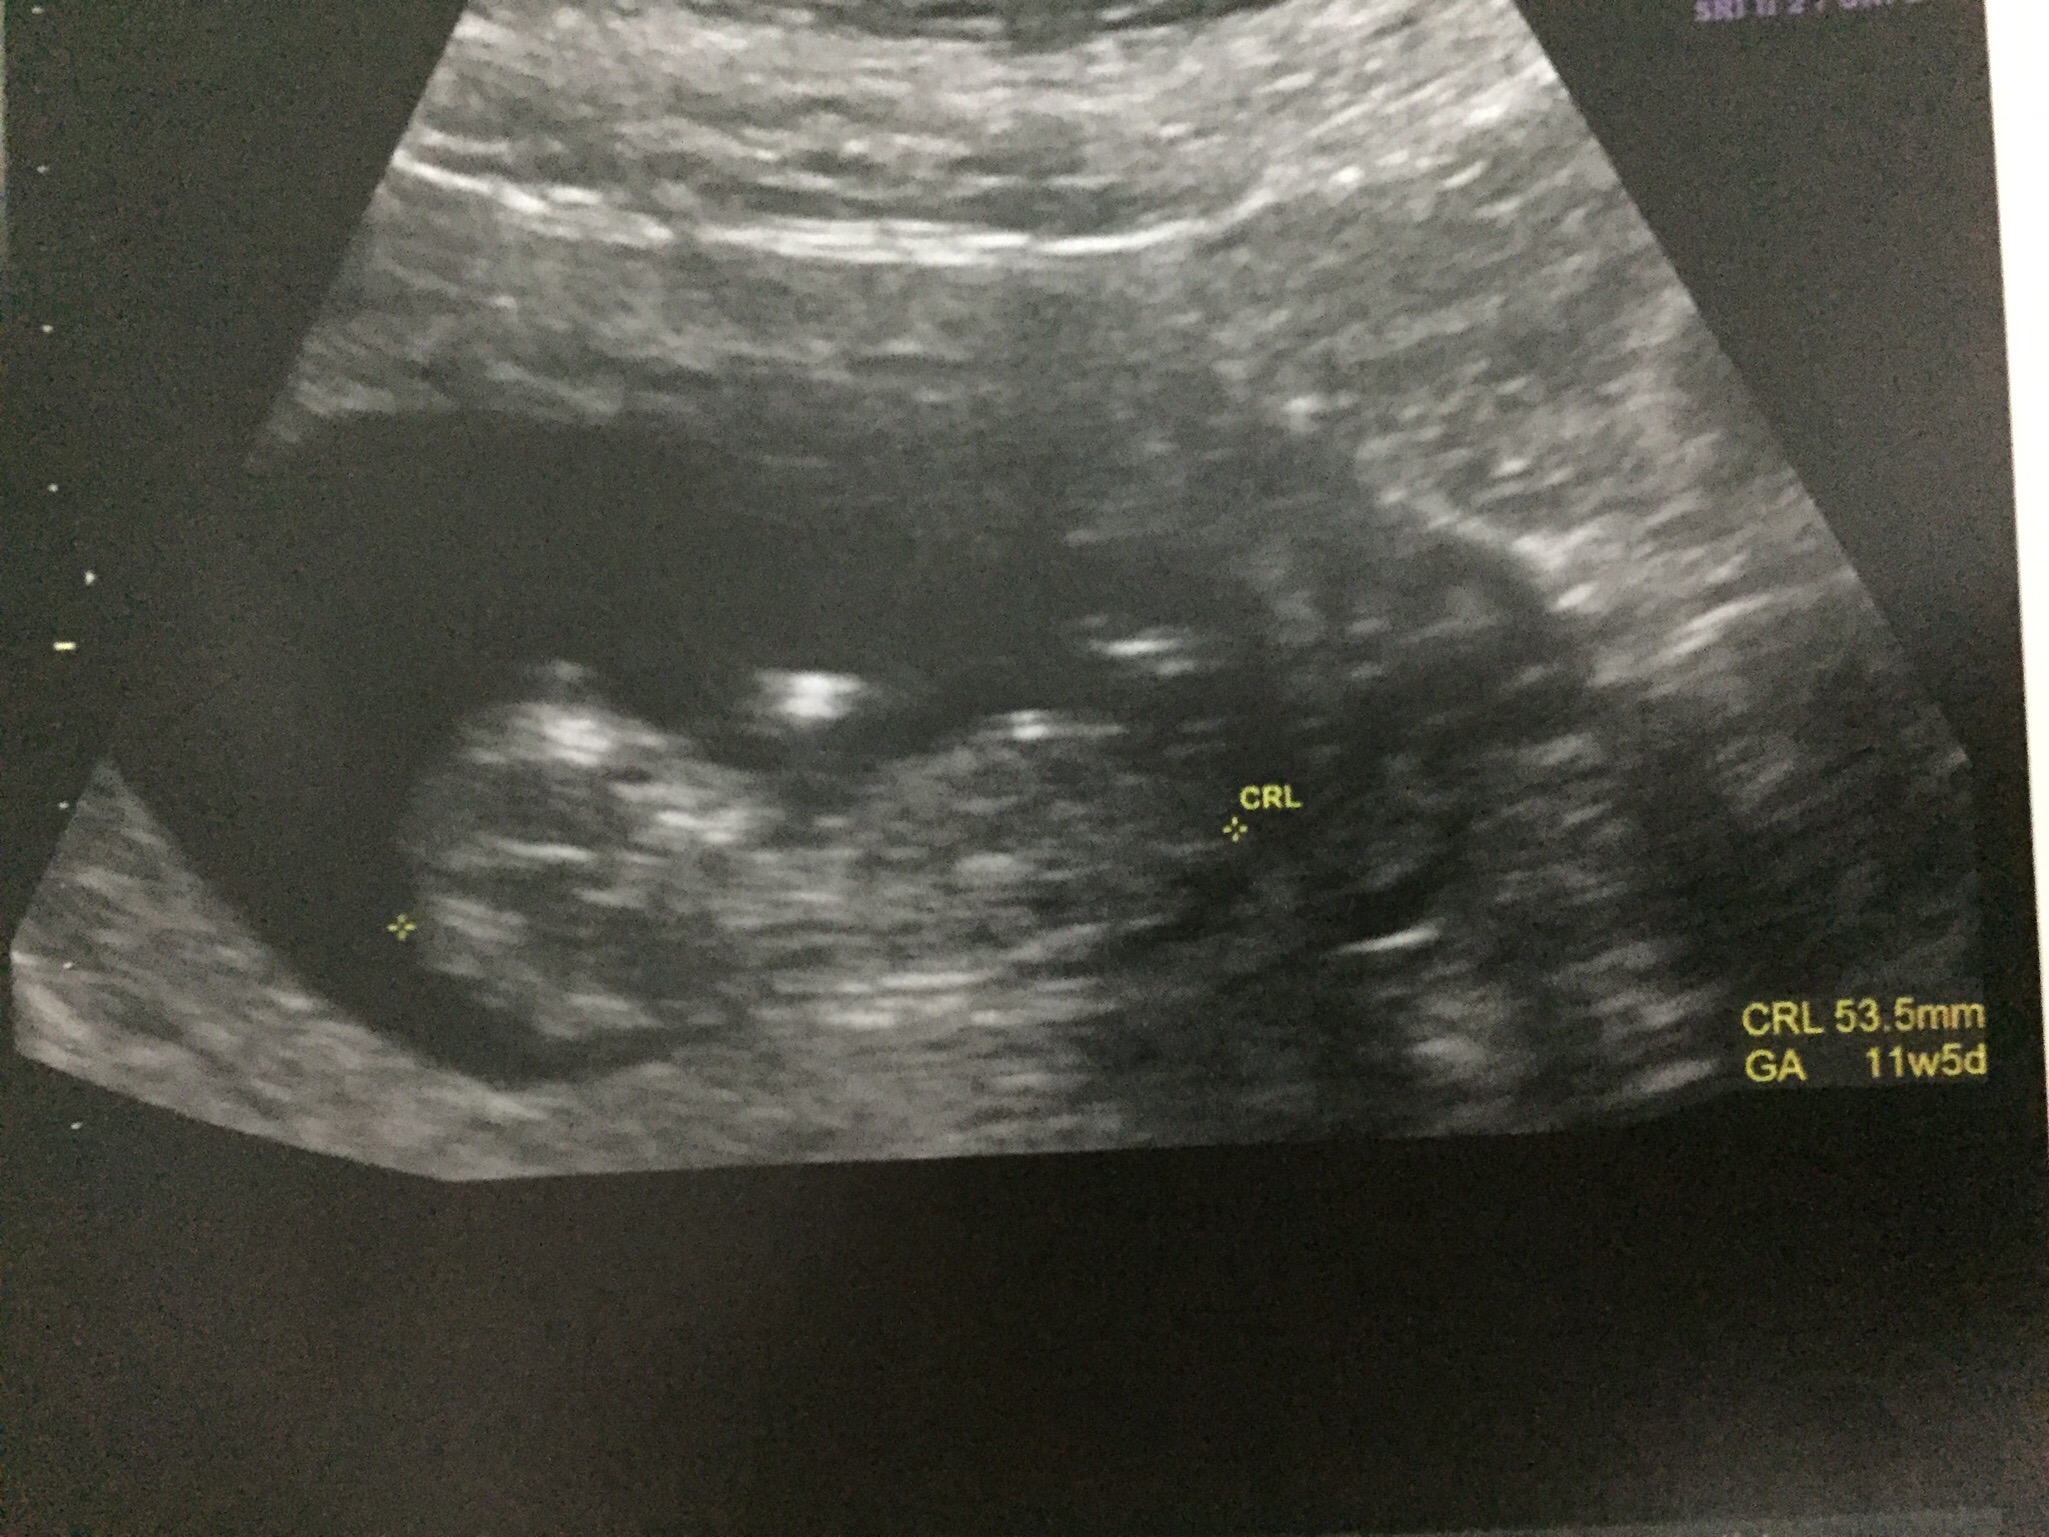

Hi! I have my gender scan tomorrow, this scan was at 11+5. Thoughts?

11+5 is too early, sorry. Can't see much gender related on these anyway. Good luck at your gender scan!